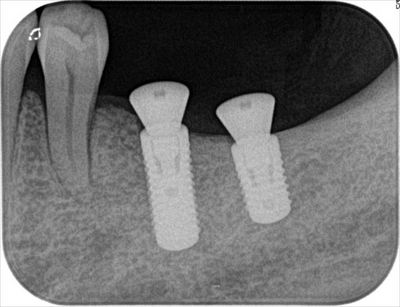

左下には2本のインプラントを埋入しました。Φ4.8mm 長さ12mmと10mmです。

インプラントの下部にうっすら黒く見える横筋が下歯槽神経管で神経と血管が入っています。

インプラントと下歯槽神経管までの距離は2mmの安全マージンを取っています。